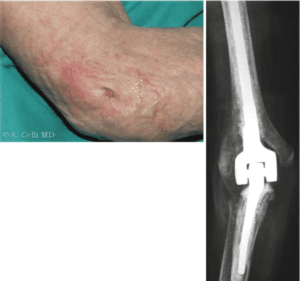

During total elbow replacement surgery, the affected portions of the humerus and ulna are substituted with artificial components.

These prosthetic elbow joints typically have a metal and plastic hinge and two metal stems.

These items are designed to fit snugly within the bone’s canal, providing stability and support.

Implants:

Metal replacement parts are typically made of chrome-cobalt alloy or titanium with a polyethene liner. Bone cement used is usually polymethylmethacrylate.